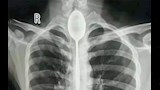

3- ملعقة مستقرة في المريء لعام كامل

في تحد غريب، ابتلع رجل صيني ملعقة بطول 20 سم، ظلت مستقرة داخل مريئه لمدة عام دون أن تسبب له آلامًا واضحة، حتى تلقى ضربة في صدره جعلته يشعر بألم شديد وصعوبة في التنفس. أُجريت له جراحة ناجحة لإزالتها.